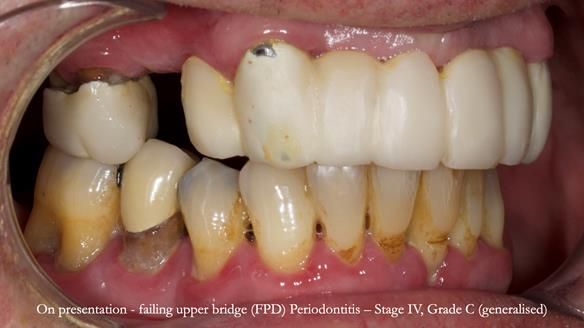

Jeremy’s upper bridge, supported by the canine teeth (13 and 23), was failing both aesthetically and functionally.

- On smiling, the bridge was clearly visible and did not look natural, as the ceramic had been ground back.

- Functionally, the bridge was unstable, due to Periodontitis – Stage IV, Grade C (generalised).

- The upper molars (UR7 and UL7) had also failed and required removal.